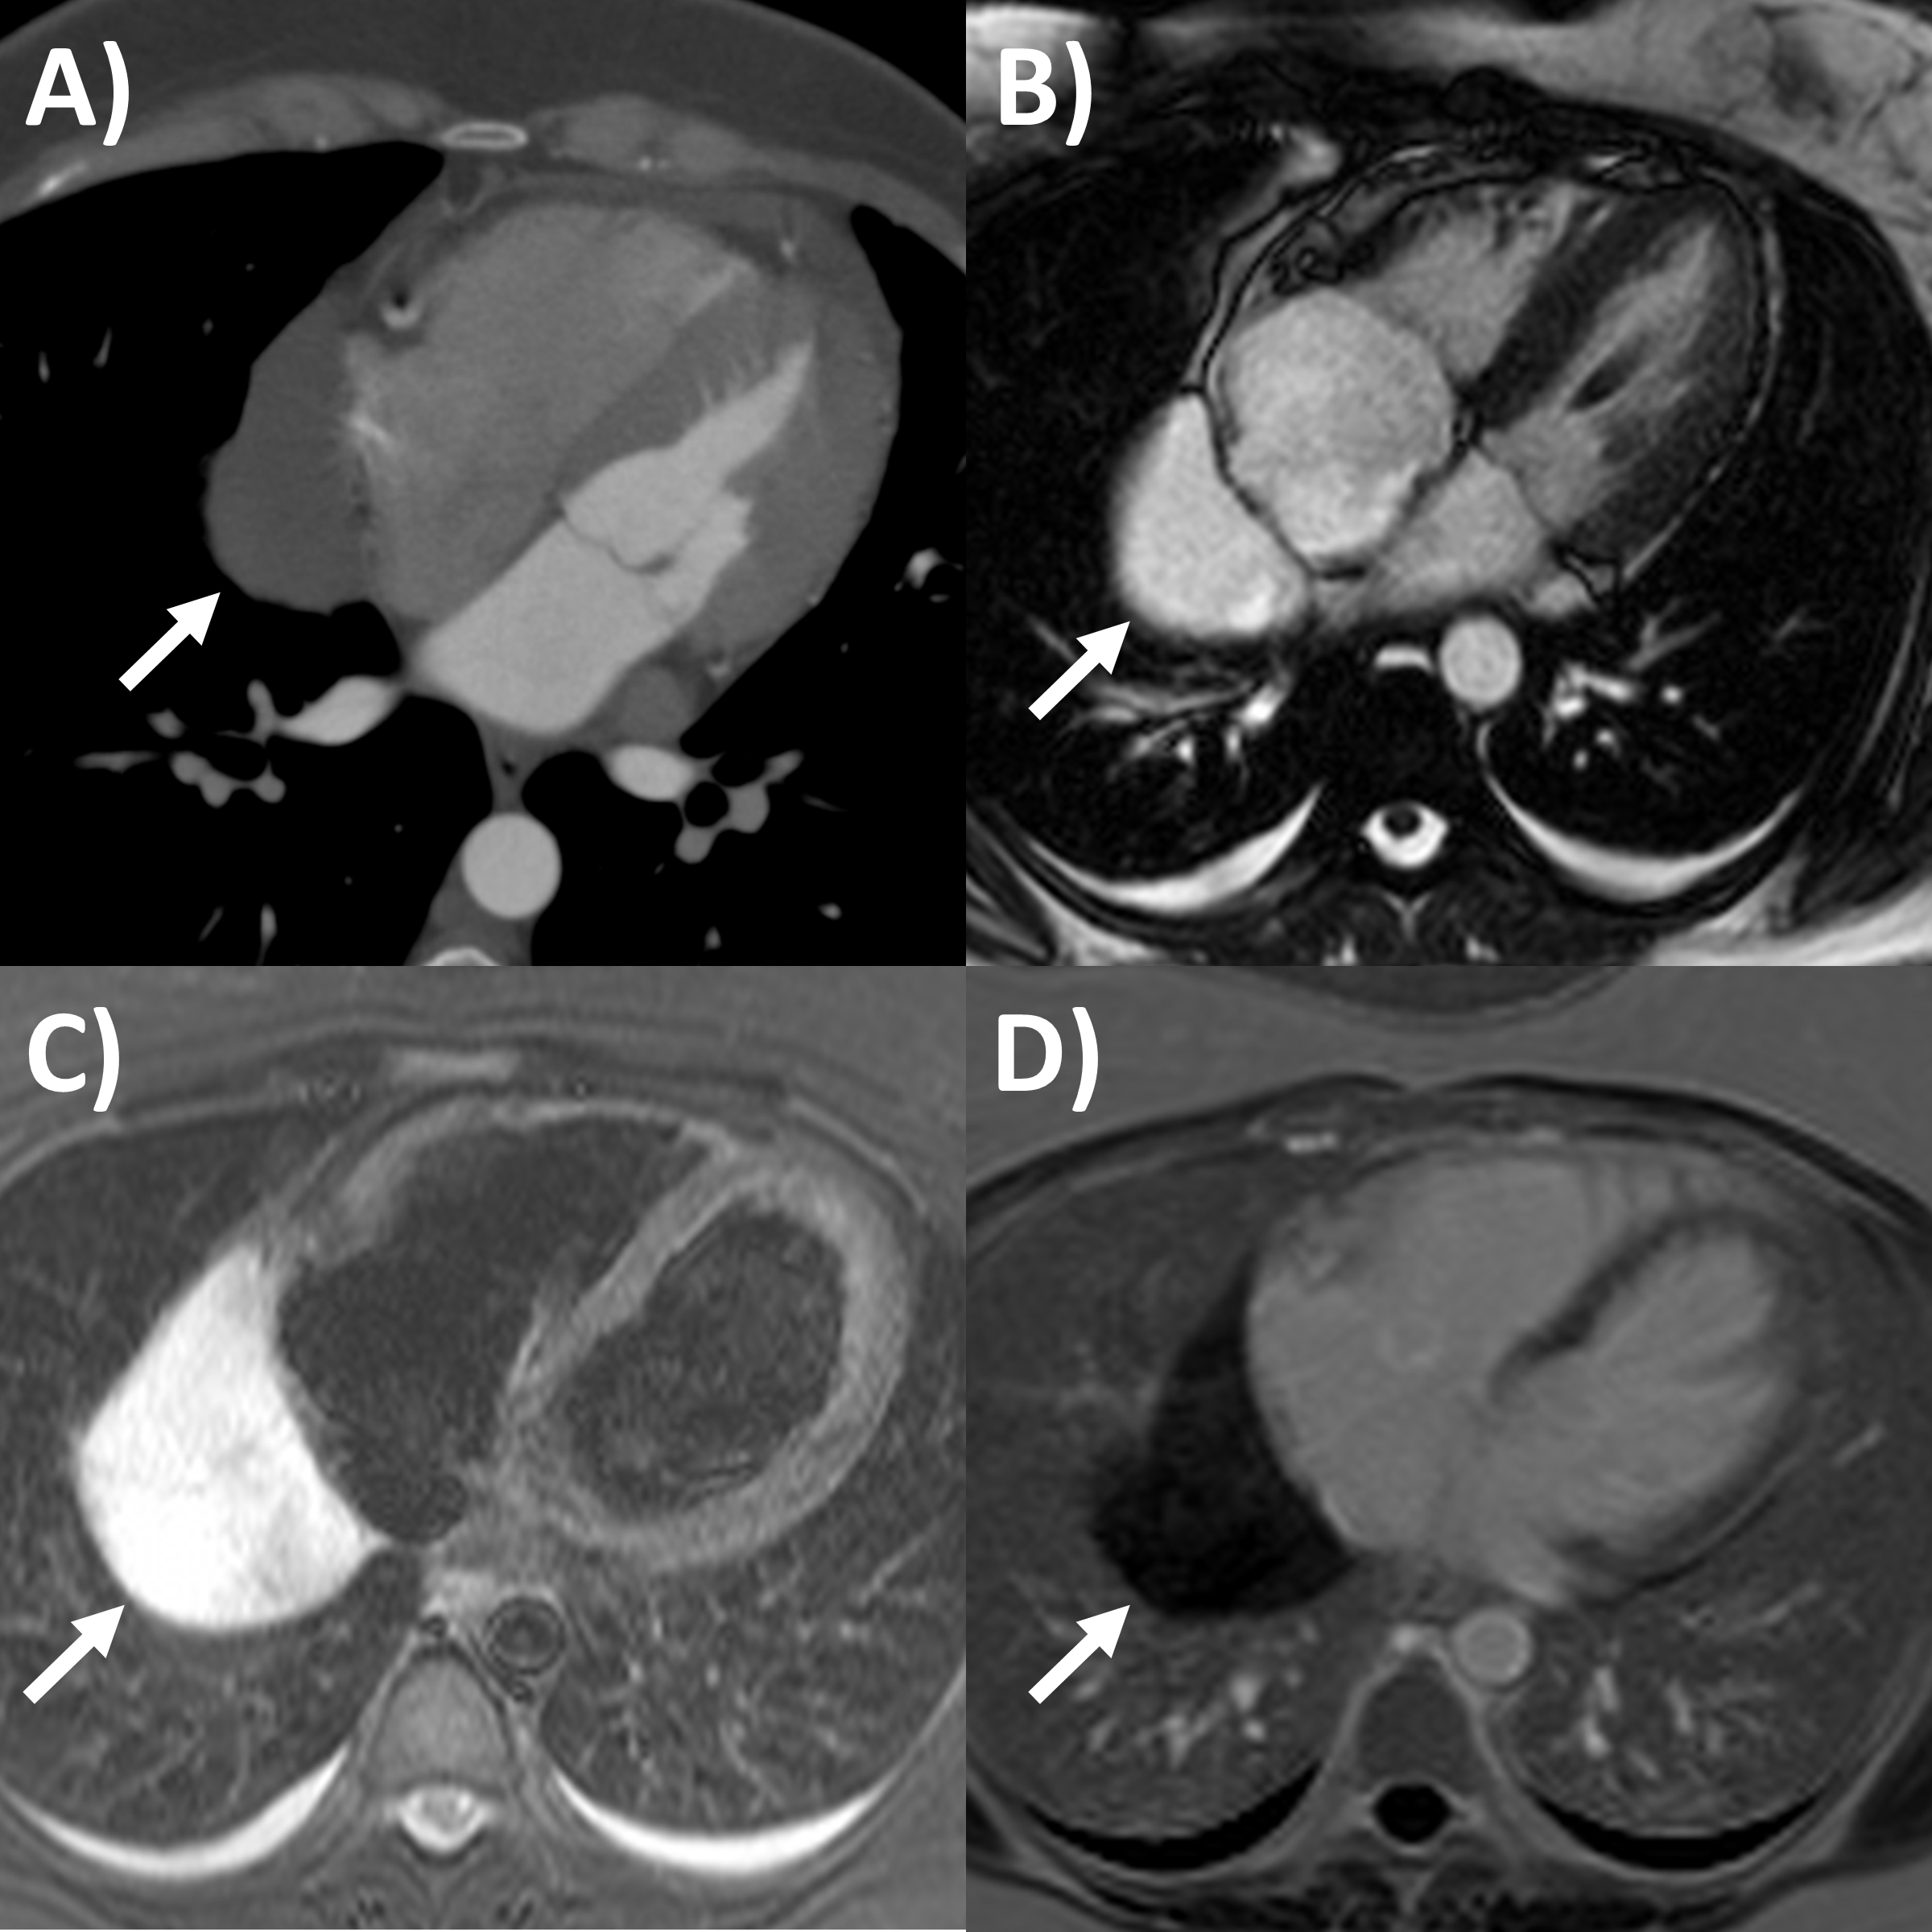

CT has greater ability for tissue characterization than echocardiography, and is able to assess the extent, local or distant spread of masses, lymph node involvement and many pericardial tumors have associated effusions that are hemorrhagic or exudative [31]. Hemangiomas appear heterogenous with contrast enhancement; lymphangiomas are heterogenous with low attenuation and septae; lipoma have low fat-level attenuation that is circumscribed, and sometimes can surround coronary arteries; teratomas usually have contain areas of calcification and fat; lymphoma are hypoattenuating with contrast enhancement; fibromas are homogeneous with no or minimal enhancement given lack of vascularity; sarcomas are broad-based masses which invade adjacent structures; and mesothelioma is seen as diffuse irregular pericardial thickening with effusion [31, 56]. Pericardial cysts are seen as a well-circumscribed homogeneous mass with thin wall on CT, with fluid density, unaffected by intravenous contrast (Fig. 4) [59, 60].

Fig. 4.Multi-modality imaging tissue characterization of pericardial cyst (arrows in all panels) adjacent to the right atrium. (A) Computed tomography axial slice, cyst was 10 Hounsfield units. (B) Magnetic resonance imaging (MRI) steady-state free precession bright blood sequence axial slice, cyst has increased signal. (C) MRI T2-short tau inversion recovery sequence, cyst has high signal. (D) MRI late gadolinium enhancement sequence axial slice, cyst has low signal.

MRI’s main advantage amongst imaging modalities is its ability in tissue characterization, and this is no different when applied to pericardial masses. Depending on tumor extension, the pericardium or myocardium may show thickening, or pericardial effusions, the latter often exudative or hemorrhagic with high signal intensity on T1-weighted sequences [31]. On T1-weighted, T2-weighted and gadolinium enhanced sequences, many tumors have low, high and high signal intensities [14, 31, 61, 62, 63]. Hemangiomas generally appear heterogeneous on all sequences, while lipomas have high signal intensity on all sequences, however its signal can be uniquely suppressed on fat-saturation pulse sequences. Fibroma have low vascularity and therefore have low signal intensity on T2-weighted sequence and none to minimal enhancement on gadolinium enhanced sequences. Mesotheliomas appear homogeneous on T1-weighted but have heterogenenous elevated signal on T2-weighte and gadolinium enhanced sequences. Of note, some studies have suggested heterogenous gadolinium uptake to indicate areas of increased lesion nodularity, growth and/or necrosis [64]. Pericardial cysts also appear as a well-circumscribed homogeneous mass with thin wall on MRI, displaying hypointense signal on T1-weighted sequence unless there is an exudative or hemorrhagic component, with hyperintense signal on T2-weighted sequence and no signal on LGE sequence (Fig. 4) [31, 65]. Lastly, pericardial hematomas show hyperintense, heterogeneous and hypointense signal on T1 and T2 weighted sequences in the acute, subacute and chronic stages, and no signal on LGE sequences regardless of timeframe [31].